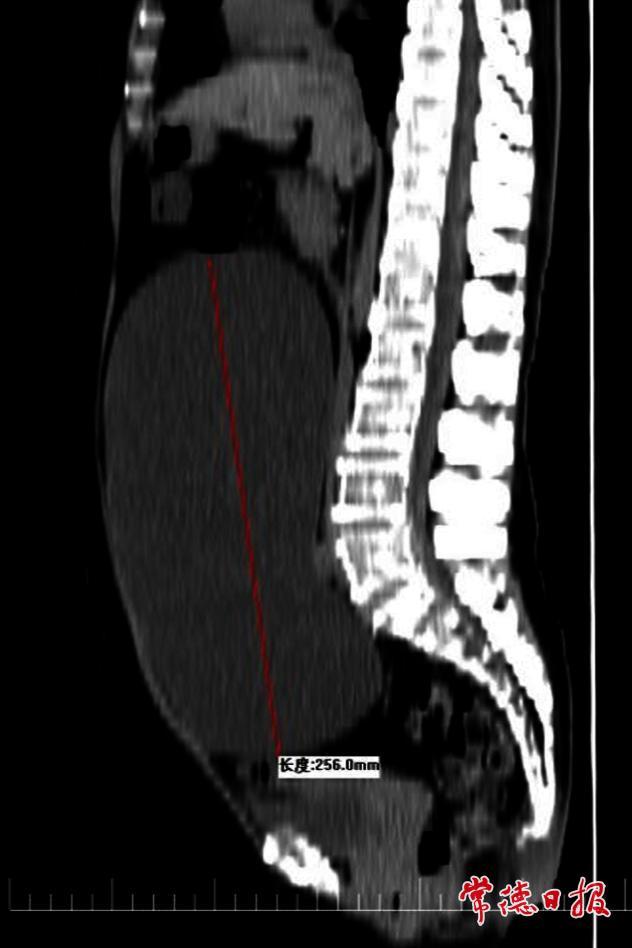

据了解,周女士在两年前开始察觉腹部逐渐隆起,起初她以为只是年龄增长导致的体重增加,并未在意。然而,随着时间推移,她的腹部明显膨隆,周女士这才意识到情况异常,随即前往医院就诊。经影像学检查,医生发现其盆腹腔内存在一个巨大的囊性包块,来源为卵巢,体积惊人,几乎占据了整个盆腹腔空间。

面对这一棘手病例,医院迅速组织多学科联合会诊(MDT)。考虑到患者年龄较大,传统开腹手术创伤大、恢复慢,可能增加术后并发症风险,医疗团队最终决定采用腹腔镜微创手术方案。该技术仅需开3至4个0.5至1厘米的小切口,既能精准切除囊肿,又能最大限度降低手术对患者身体的伤害。